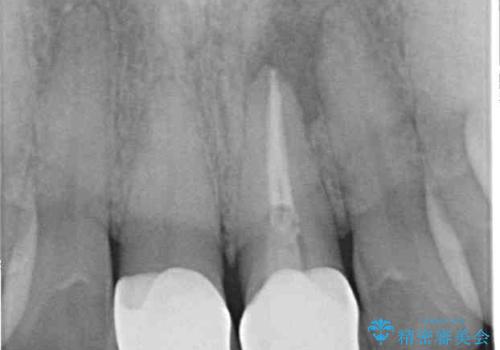

繰り返す痛み 下顎小臼歯の再根管治療